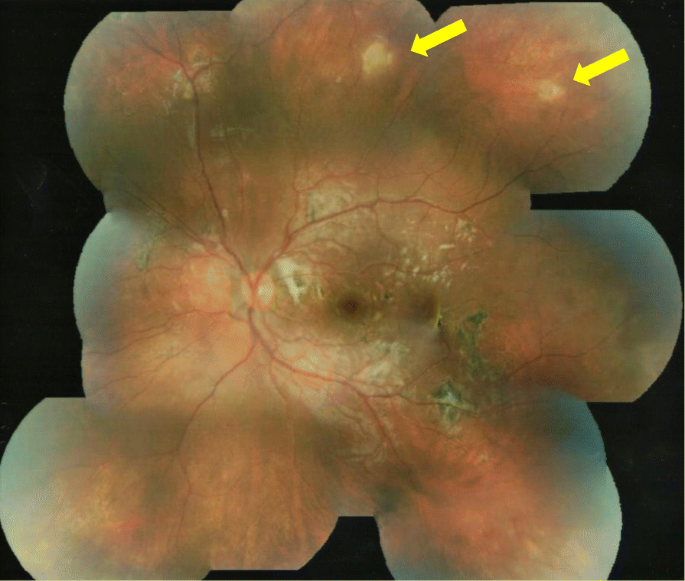

Over the following 4 months, without treatment, her vision increased in the left eye to 6/12 unaided and the fundal appearance improved showing reduced sub-retinal infiltration; however, a focal circular area of chorioretinitis developed along the superotemporal arcade (Fig. 2). One month later, the circular area of chorioretinitis had faded but a new active area of chorioretinitis was noted superior to the disc. Within this area, an elongated, white, glistening nematode was identified with an estimated size of 1500 μm when compared with the optic disc diameter (Fig. 3). Ocular coherence tomography horizontally through this new area of active chorioretinitis indicated a nematode with tapered end curling upwards from subretinal space into deep retinal layers (Fig. 4). This led to a working diagnosis of diffuse unilateral subacute neuroretinitis (DUSN).

Colour fundal photograph of left eye 5 months following presentation demonstrating mild but reduced optic disc oedema, white subretinal fibrosis temporal to the disc, scattered retinal pigment epithelial proliferation (pigmented scars) and an active area of chorioretinitis superior to the disc with a white glistening nematode as indicated by the yellow arrow

Following diagnosis of DUSN, diode laser was performed under general anaesthetic to the superior area of active chorioretinitis and presumed nematode. The patient was also commenced on oral albendazole 200 mg twice daily for 1 month and a reducing course of oral prednisolone starting at 25 mg daily and tapered over 30 days. After another month, her visual acuity had improved further to 6/9 and the treated area of chorioretinitis superior to the optic disc had disappeared. However, new areas of chorioretinitis had appeared temporal to the superotemporal arcade and in the inferonasal fundus (Fig. 5). A further course of oral albendazole 200 mg twice daily and oral prednisolone 7.5 mg was commenced and planned for 30 days but was discontinued by the patient after 2 weeks. After a further 2 months, the fundal appearance had changed once again and new areas of chorioretinitis had appeared in the superotemporal retina with resolution of the areas inferonasally and temporal to the superotemporal arcade (Fig. 6). Further laser was administered to the new superior lesion where a nematode was suspected. Despite additional anti-helminthic treatment with ivermectin, recurrence of active chorioretinitis lesions continued and electrophysiology testing indicated significant left retinal dysfunction.